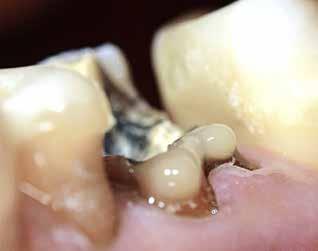

Knækket rodfil

i distal kanal -6

PATIENTTILFÆLDE

Patienten henvender sig på klinikken pga. akutte smerter fra -6. Der laves akut oplukning og findes tre kanaler. Ved udrensning i distale kanal for at finde endeligt rodmål knækker ca. 1-2 mm af fil 08 i kanalen. Patienten bliver informeret og henvist til specialtandlæge for videre behandling.

LÆRING

Det fremgår, at der er tale om en filstørrelse 08, altså den tyndeste fil, der findes. Ved flerrodede tænder med lange, krumme og/eller oblitererede (“tilgroede”) rodkanaler er risikoen for filfraktur højere.

Det anbefales derfor, at du anvender meget fleksible file, skyller kanalerne hyppigt undervejs og kasserer file, der udviser svaghedstegn (fx vrid eller buk på filens arbejdende del). Du bør desuden kassere de mindste file efter brug, da risiko for usynlige svagheder i disse er høj. Alternativt kan du henvise til en tandlæge med særlig kompetence inden for rodbehandling, hvis du vurderer, at en rodbehandling er særligt vanskelig.

Se også guiden "Sådan fjerner du et filfragment" på side 774.